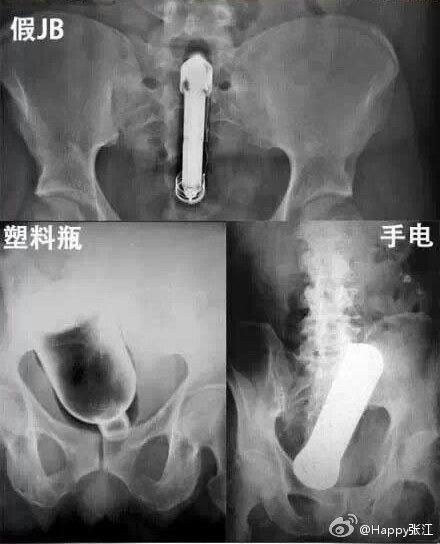

据说这是医生们盘点的肛门塞入东西的奇葩之最,毁三观啊